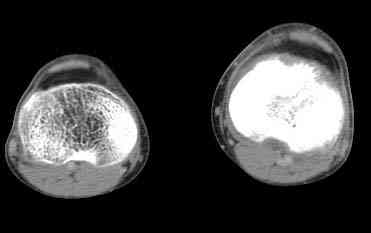

важаемые коллеги! Поступил больной 22 лет. Болен с января 2006 - появились боли в области верхнейтрети голени. При первичном осмотре в поликлинике был заподозрен первично-хронический остеомиелит - осмотрен гнойным хирургом - произведена биосия . Заключение - хондросаркома. Осмотрен онкологом - с учетом характера опухоли - химиотерапия, лучевое лечение не показано. Предложена либо ампутация, либо решение вопроса о возможности выполнения органосохраняющей операции. При обращении к нам произведена сцинтиграфия скелета - зоны гиперфиксации РФП: верхняя треть голени- 960%, нижняя треть бедра - 380%, Дистальный метафиз голени и затылочная область - 140%. В легких - метастазов нет. Произведена КТ (картинки в приложении). Учитывая абсолютную нестыковку рентгенологических и морфологических данных повторно биопсия. Выявлено, что первичная биопсия выполнялась из поверхностной параоссальной зоны - там локализованы хрящеподобные массы, далее очень плотная кость без хрящевых участков - биоптат взят фрезой с большим трудом. Морфологического заключения пока нет. Хотелось бы узнать Ваши варианты диагноза и соответственно тактику.

Не специалист по онко ортопедии, но по локализации (бедро, большеберцовая и плечевая кость), возрасть, в данный момент отсутствия метастаза и формация новой кости с мягкотканним вовлеченим, процесс больше напоминает остеосаркому большеберцовой кости.